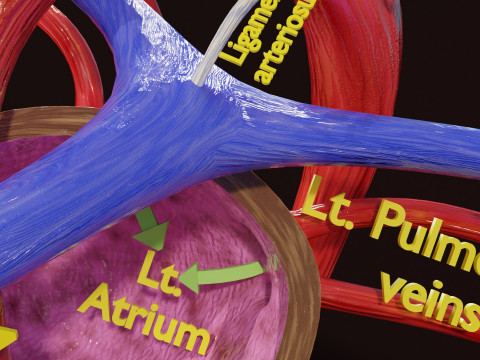

The model meshes include adult circulation versus circulation in Tetralogy of Fallot (TAF), arrow labels and text labels. The blood flow in a patient with Tetralogy of Fallot is outlined in this model. To contrast it to normal blood circulation a separate model of normal circulation is included. The Tetralogy of Fallot (OVER RIDING OF AORTA, PUL STENOSIS, VENTRICULAR SEPTAL DEFECT, RIGHT VENTRICULAR HYPERTROPHY), fossa, ligament teres , venosus, and arteriosus are duly depicted with proper labelling and blood flow directional arrows. Excellent model for teaching, demonstration and knowlegde of human body. The models include both procedural and image textures blend files separately. The texture file include diffuse, roughness and normal png and jpeg based on non overlapping UV maps.